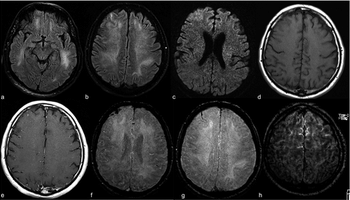

Images similar to those found in patients with anosmia associated with other types of coronavirus infections.